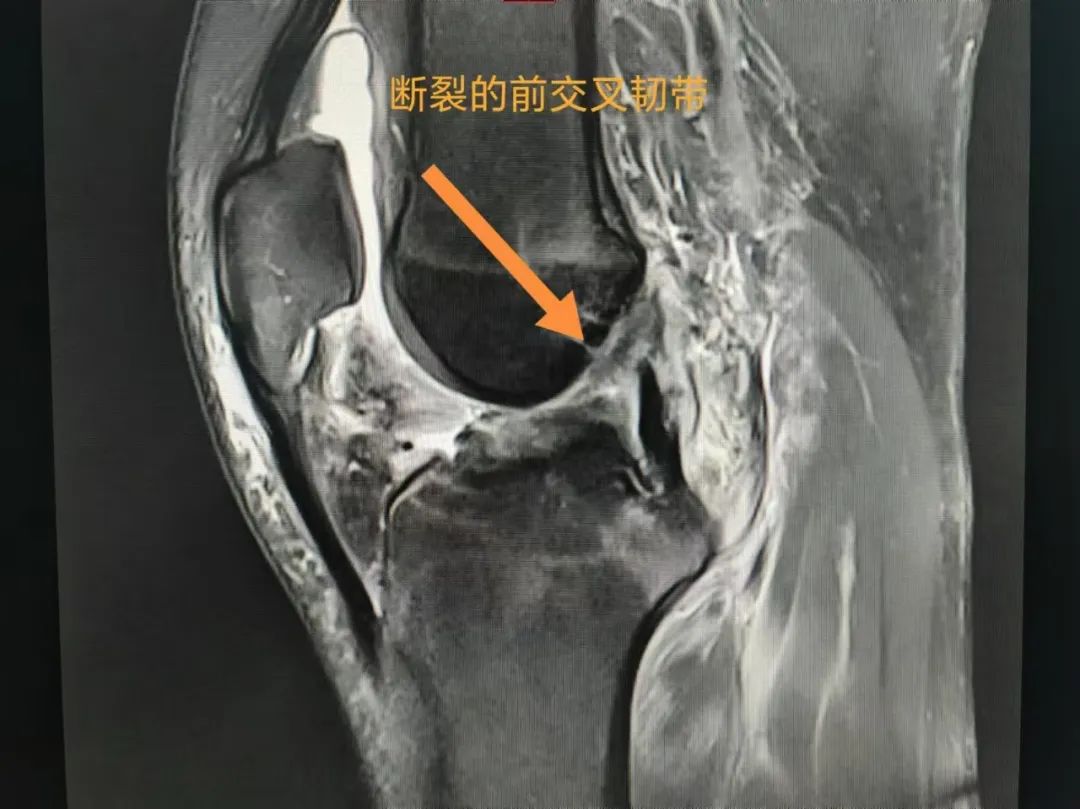

【中心医院·医者红】18岁小伙打球扭...